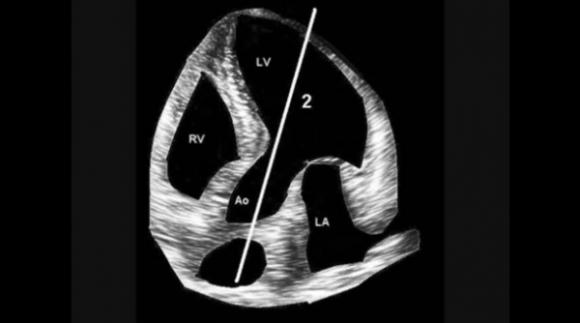

Medico Argentino desarrolla un nuevo método de auscultación cardíaca innovando en el procedimiento luego de 200 años‏

Un nuevo estetoscopio basado en una física distinta del clásico fue desarrollado por un médico argentino. Detecta cosas distintas del ya conocido. Sirve para auscultar el corazón humano y las arterias y venas de todo el...